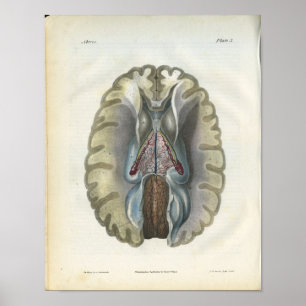

Impressão

Preço23,90 €